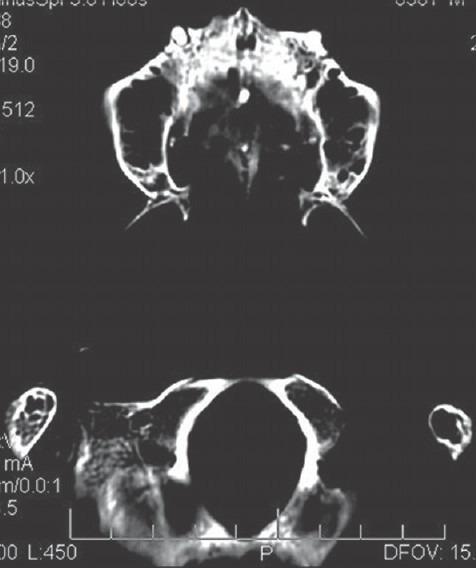

The Department of Orthodontics and Dentofacial Orthopedics at Government Dental College and Hospital, Nagpur. The study was done on an analytical model developed from a dry human skull of an adult female with an approximate age of 20 years.

A 3D finite element analysis of the craniofacial complex was developed from sequential computed tomography scan images. Known transversal (X) displacement with magnitudes of 1, 3, and 5 mm were applied and the displacement and Von-Mises stresses in different planes were studied on different nodes located at various structures of the craniofacial complex.

那格浦尔政府牙科学院和医院的正畸与牙颌面矫形科。该研究是在一个由一名年龄约20岁的成年女性干燥人类头骨开发的分析模型上进行的。

从连续的计算机断层扫描图像中开发颅面复合体的三维有限元分析。施加大小为1、3和5毫米的已知横向(X)位移,并在位于颅面复合体各种结构的不同节点上研究不同平面中的位移和冯·米塞斯应力。